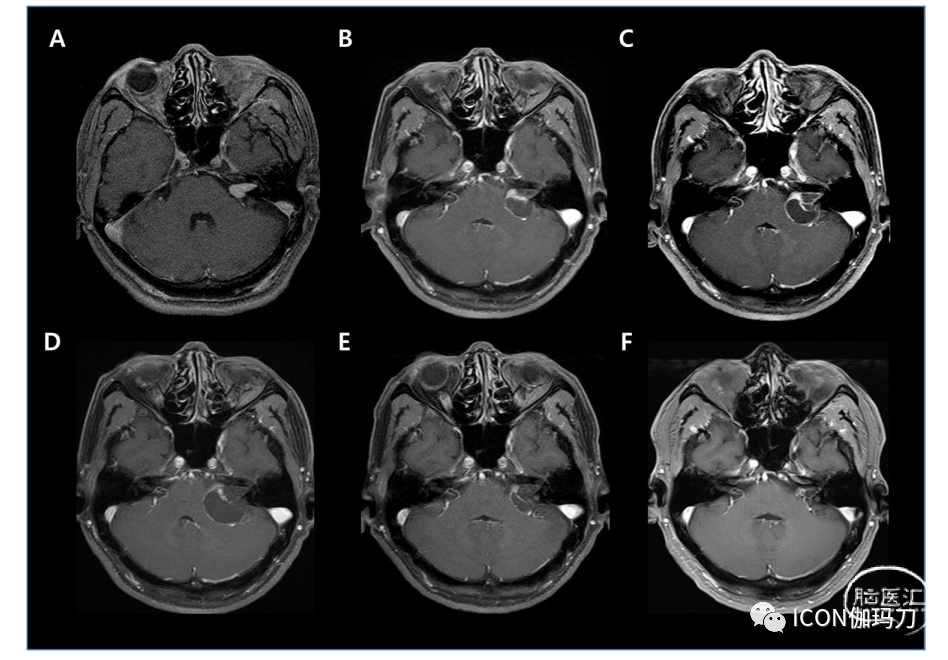

图1对比增强MRI上VS的一系列变化和IAC的表现。A:2006年5月,在左侧IAC发现一个1.6 cm的均匀性肿块,并延伸至同侧CPA池。到2009年6月(随访第3年),肿瘤体积开始增加到3.9 cc,伴随实性部分减少和囊性部分增加。C. 2010年6月,病灶进一步增大至2.5×2.3×2.1 cm3,内部有囊性改变,IAC增大。肿瘤体积6.4 cc。期间患者主诉听力下降、间歇性头晕、间歇性步态障碍。D. 2011年4月肿瘤增大至2.9×2.7×2.6 cm3,囊性增大进展,伴IAC扩大。肿瘤体积最大达10.8 cc。患者症状无加重。E. 2013年5月,肿瘤缩小至1.8×1.6×1.6 cm3,体积5.0 cc,此时患者间歇性症状好转。F. 2020年6月,肿瘤进一步缩小至1.5×1.3×0.8 cm3,体积为0.3 cc,随访期间首次体积小于GKRS治疗前体积。

患者接受GKRS (12 Gy;等剂量线,50%)。术前耳鸣体积为0.8 cc,术后耳鸣持续约1个月后好转。术后6个月复查MRI未见体积变化及内部坏死。在每年的随访MRI中,在第3年观察到囊性改变,肿瘤体积开始增大至3.9 cc(图1B)。此时听力维持在PTA为50 dB, SDT为90%。然而,GKRS治疗后3.5年,他失去了听力,再也没有恢复。4年随访时,肿瘤体积迅速增加至6.4 cc,并伴有间歇性头晕和步态障碍(图1C)。然而,他没有其他小脑症状,能够进行日常活动。直到第5年,肿瘤体积继续增大,最大体积为10.8 cc(图1D)。他的间歇性症状仍然存在,但没有出现或恶化症状,因此不需要手术。在下次随访之前,我们同意在症状恶化时选择手术。幸运的是,在1年后的第二次随访中,肿瘤体积开始缩小至7.3 cc,第7年进一步缩小至5.0 cc。患者的间歇性症状随后也有所改善(图1E)。此后肿瘤大小继续减小,最终在第14年时小于初始大小(图1F)。目前,他没有任何症状。